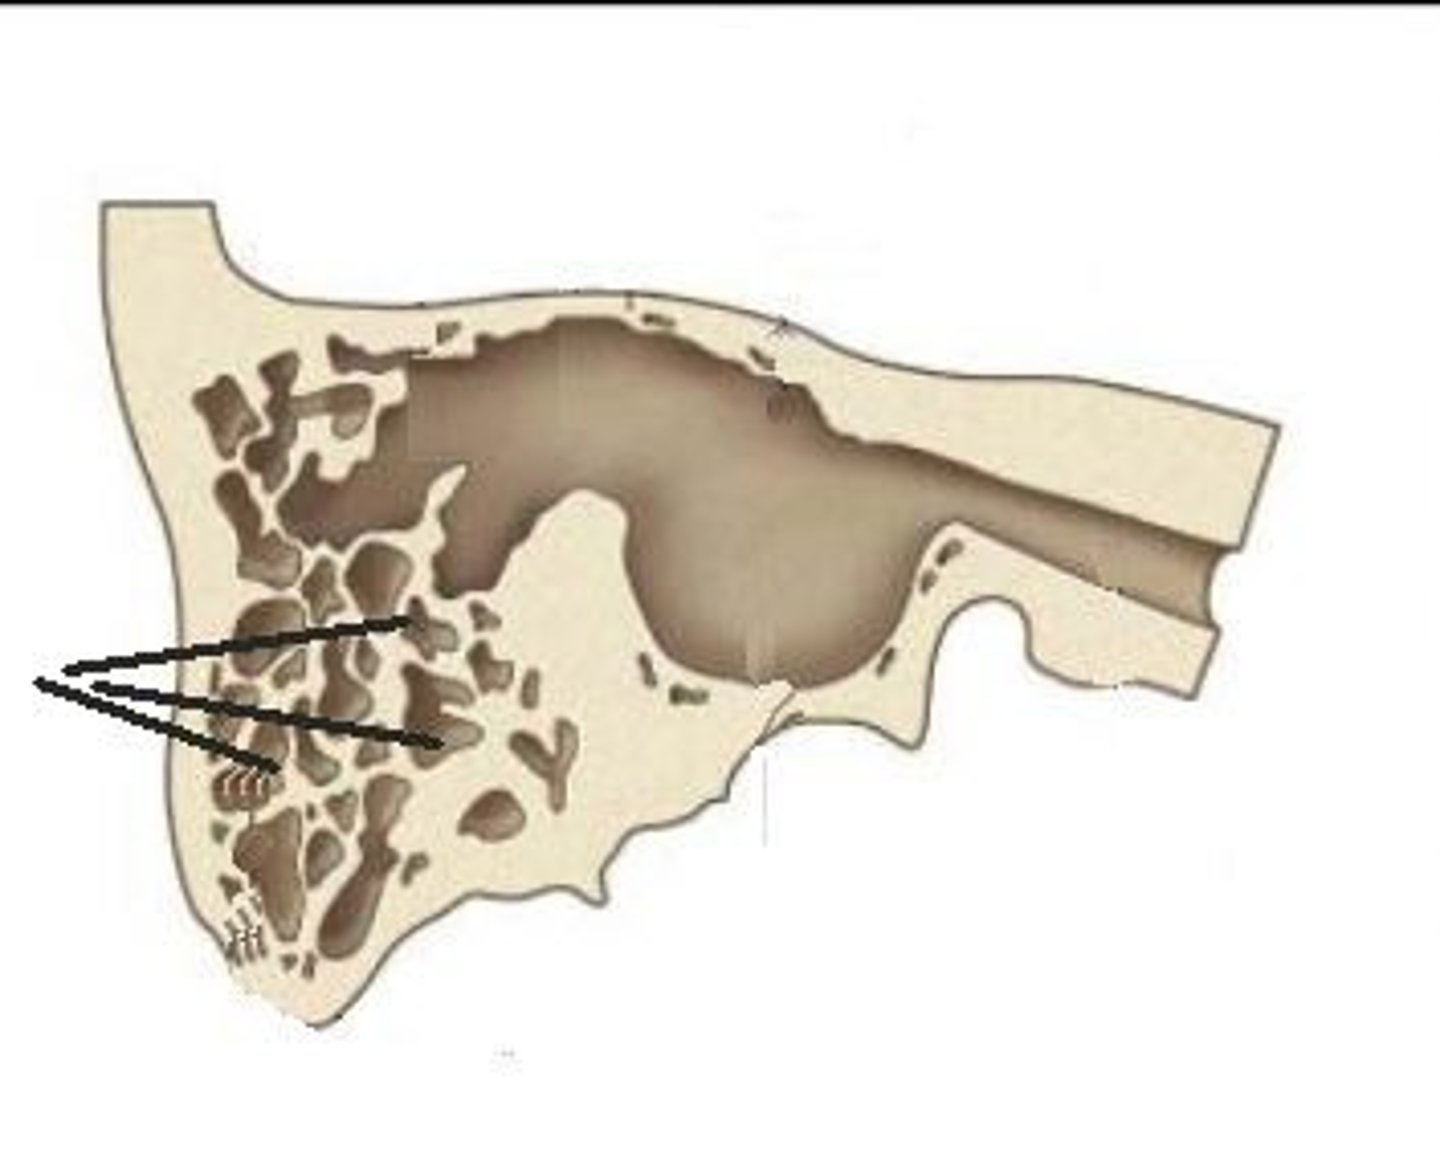

mastoid air cells